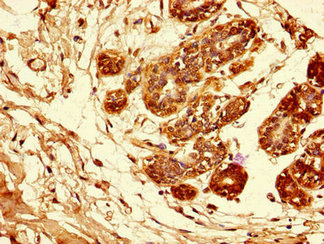

Immunohistochemistry of paraffin-embedded human breast cancer using CSB-PA11339A0Rb at dilution of 1:100